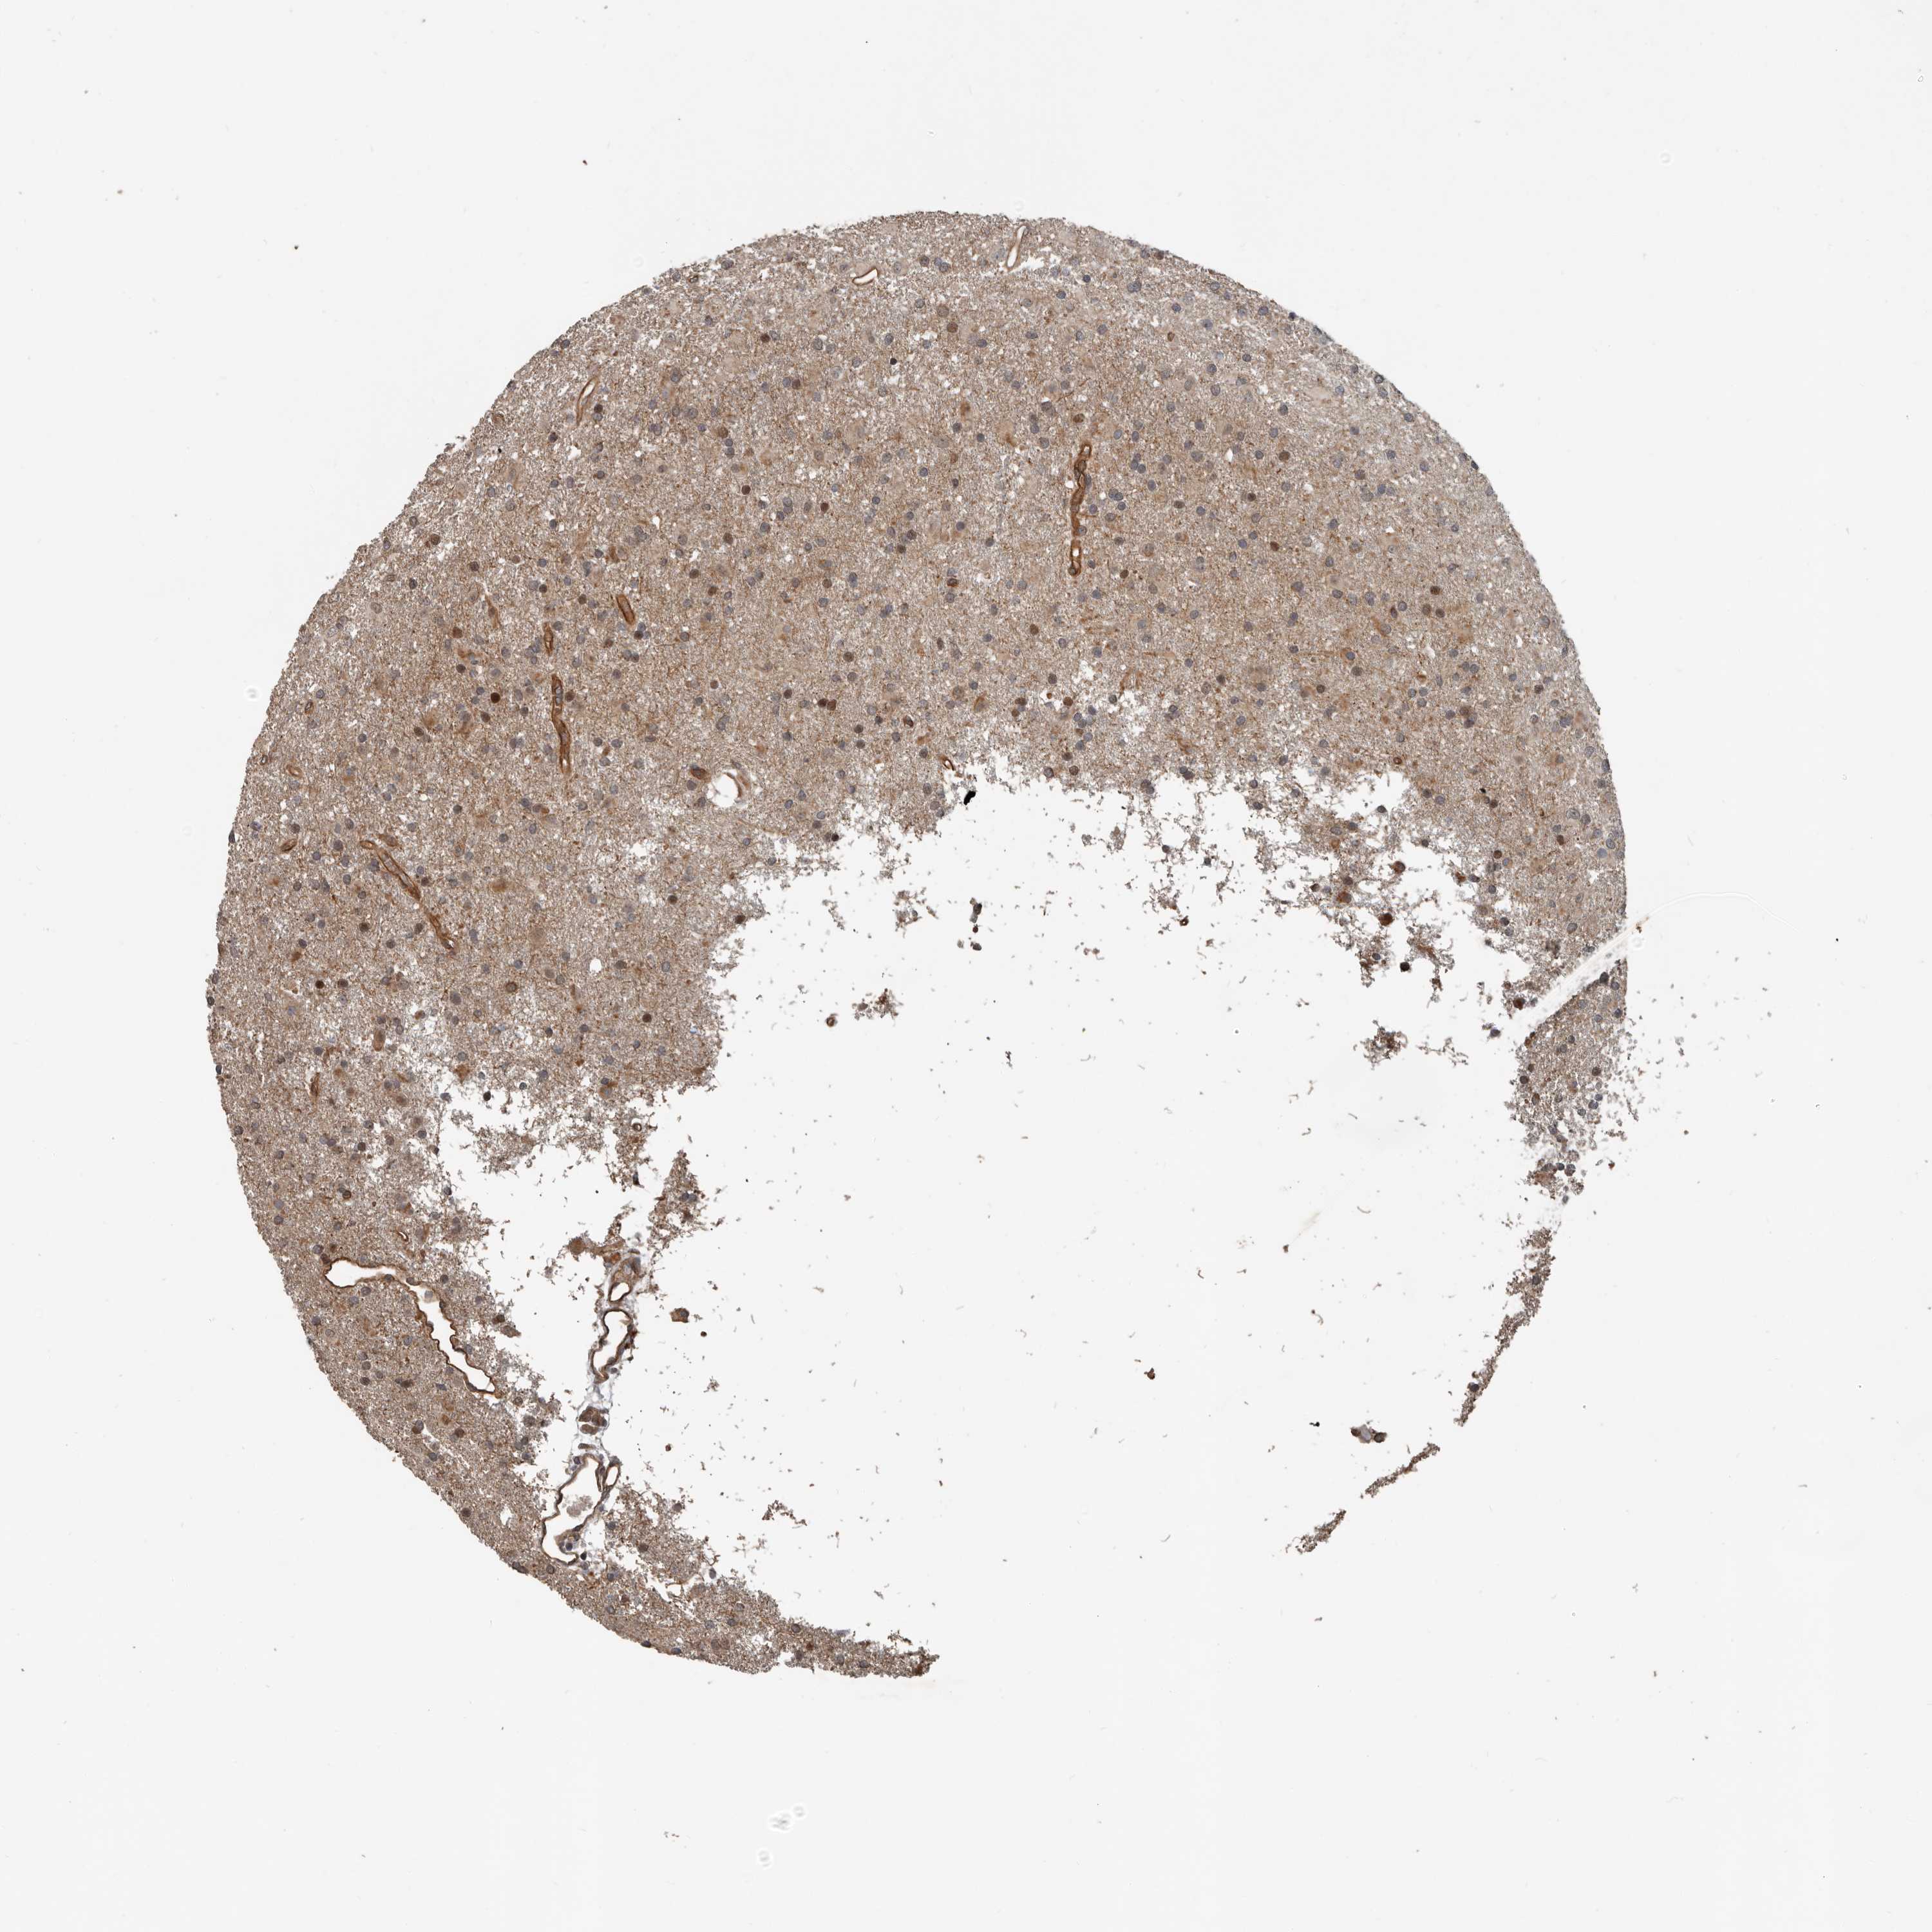

GLIOMA - Protein expressioni

A mouse-over function shows sample information and annotation data. Click on an image to view it in a full screen mode. Samples can be filtered based on level of antibody staining by selecting one or several of the following categories: high, medium, low and not detected. The assay and annotation is described here.

Note that samples used for immunohistochemistry by the Human Protein Atlas do not correspond to samples in the TCGA dataset.

Antibody stainingi

Antibody staining in the annotated cell types in the current human tissue is reported as not detected, low, medium, or high, based on conventional immunohistochemistry profiling in selected tissues. This score is based on the combination of the staining intensity and fraction of stained cells.

Each image is clickable and will lead to virtual microscopy that enables deeper exploration of all samples and also displays staining intensity scores, fraction scores and subcellular localization as well as patient and tissue information for each sample.

Antibody HPA028400

Antibody HPA028439

Glioma, malignant, High grade

Glioma, malignant, Low grade